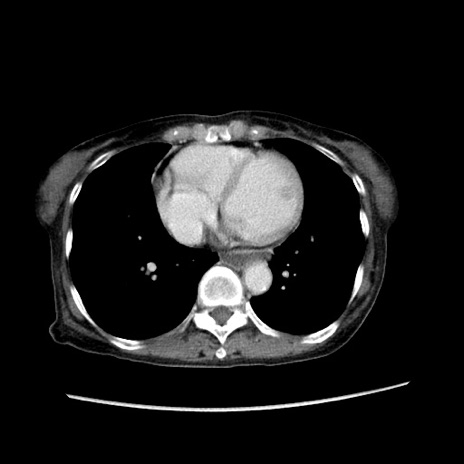

冠状断像

症例25(横断像)

【症例】80歳代女性

【主訴】胸のつかえ感

【現病歴】約9時間前に食後から胸のつかえた感じあり、嘔吐あり、来院。

【既往歴】胃癌(全摘)、胆摘、虫垂炎

【身体所見】心窩部に圧痛あり、反跳痛なし。

【データ】WBC 5700、CRP 0.05